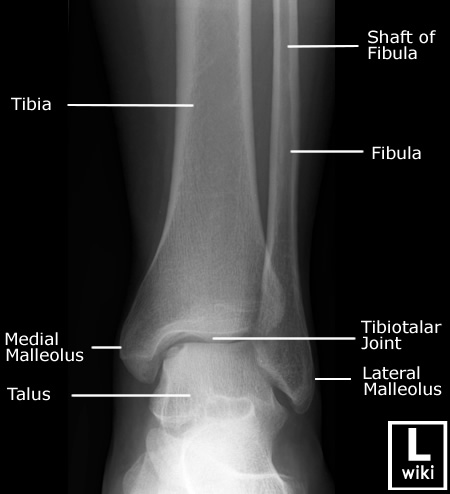

| [Anatomy] Ankle(발목) (0) | 2024.01.25 |